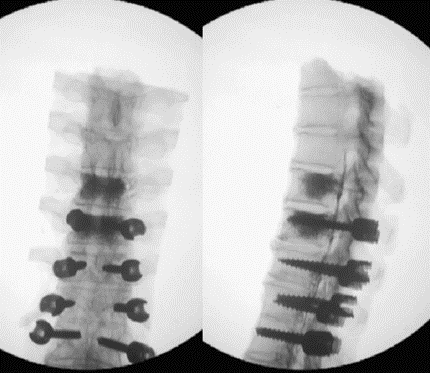

(3)肋骨固定

T10骨盆固定,出现交界性后凸

行翻修手术:T9/10SP截骨,延长到T4固定,预防性双侧肋骨固定(VEPTR)

图32-33 肋骨固定